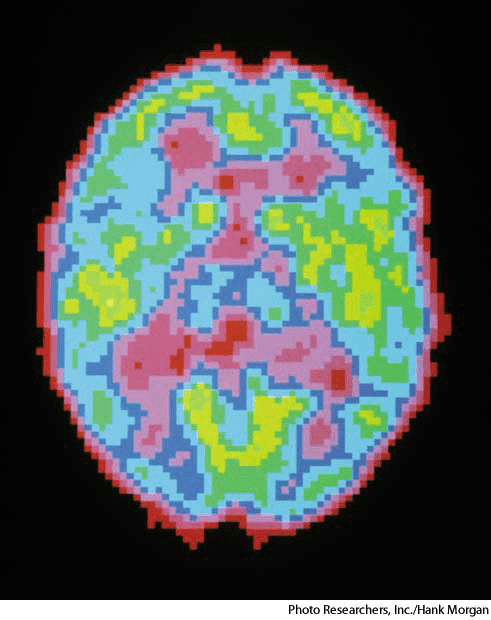

positron emission tomographyn.(名词)abbr. PET【缩写】 positron emission tomographyscan of a human brain during sleep- Tomography in which a computer-generated image of a biological activity within the body is produced through the detection of gamma rays that are emitted when introduced radionuclides decay and release positrons.正电子发射X射线层析照相术:照相术,通过引进的放射性核素发生衰变而释放的正电子发射的伽玛射线来探测体内的生理活动,并通过计算机将其成像